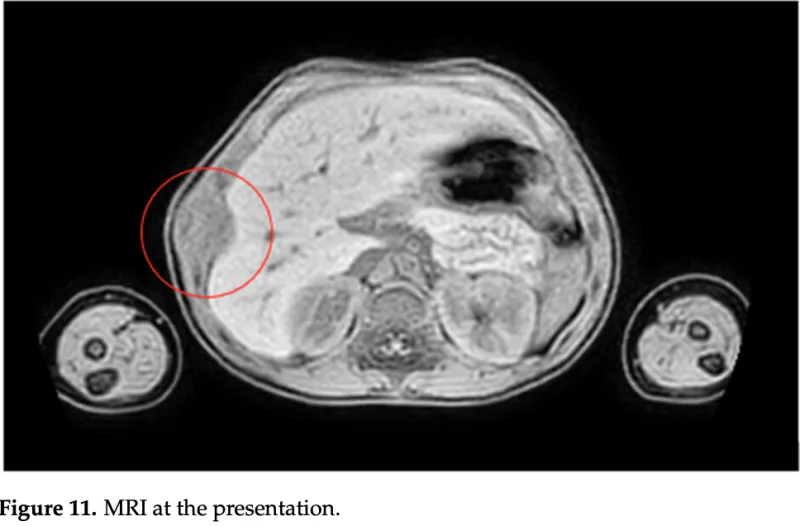

骨が壊れていて, その周りに腫瘤(骨外腫瘍)が形成されています.

肋骨の内側と外側に腫瘤の形成が認められます.

引用元:Salimbene O. Primary chest wall Ewing sarcoma: Treatment and long-term results. Life 2024. 14.

最後に肋骨腫瘍の若年患者さんの造影MRIを確認. 骨内から骨外へ進展する腫瘍を認め, ユーイング肉腫を強く疑いました. 大学病院整形外科での診察を手配しました.